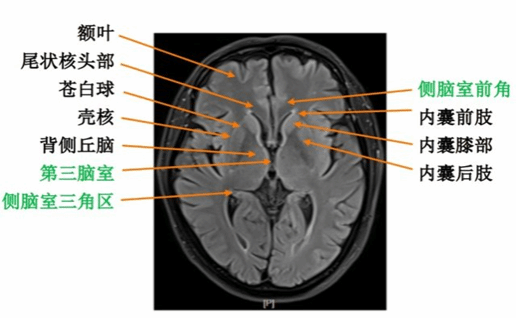

② 医学影像数据的可视化

借助医学影像处理技术,将CT、MRI等医学影像数据转换为三维立体模型。在虚拟仿真系统中,学生可以直观地观察脑部解剖结构、病灶位置和血管分布等关键信息。医学影像数据的可视化有助于学生更好地理解手术区域,提高手术的准确性和安全性。